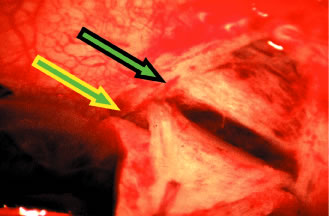

To obtain increasingly lower IOP, it is necessary to modify surgical technique (Table 15). By performing guarded filtration procedures so that the sutures can be released postoperatively, with the use of either laserable or releasable sutures, a lower final IOP can be obtained in some cases. This technique allows a bleb to develop that is similar to that seen in a full-thickness filtration procedure. Such blebs tend to be thin, polycystic, and located directly at the limbus, in contrast to those seen after classic trabeculectomy, which are thicker, lower, more diffuse, and more posterior. When antifibrosis agents (antimetabolites and corticosteroids) are added to procedures designed to develop full-thickness filtration, IOP tends to be sharply reduced.27–29 The blebs associated with the use of 5-fluorouracil (5-FU) and mitomycin are an exaggeration of the full-thickness type of bleb: Often, they are extensive, sometimes involving 360 degrees of the anterior surface of the globe, and the conjunctiva tends to be thin and completely ischemic.30–34

The thin filtration blebs associated with the use of mitomycin or 5-FU may rupture spontaneously. They tend to be so high that the adjacent cornea becomes dry, with the development of an uncomfortable delle. Ptosis tends to develop, and patients often are photophobia One of the most serious concerns is the high incidence of endophthalmitis in patients with thin blebs. When full-thickness blebs were the routine type of glaucoma procedure, endophthalmitis would develop in approximately 1% of patients. When 5-FU was used to develop filtration blebs inferiorly, an 8% rate of endophthalmitis was reported.35–42 Hypotony, even in the absence of a thin bleb, introduces serious problems. The soft eye does not maintain a constant optical state, and it has a constantly changing amount of astigmatism that makes it impossible to correct. Each time the patient blinks, the amount of astigmatism changes. Macular and disc edema cause reduced central acuity and deterioration of the visual field, and the globe may have a constant, visceral ache. Patients with such eyes are not comfortable.